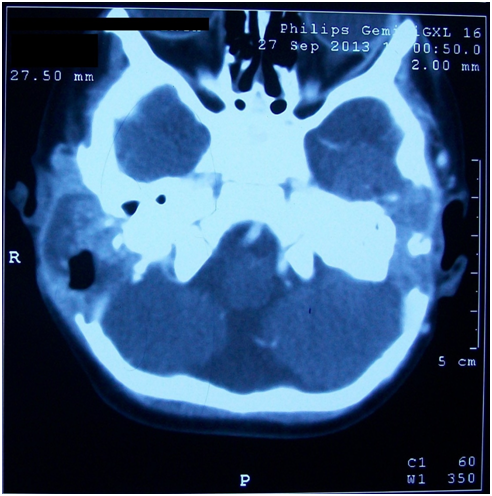

Urine routine examination was within normal limits. C reactive protein was 4.8 mg/dl (positive >0.6). A contrast enhanced computerized tomography (CT) scan of the temporal bone showed bilateral ottitis media with erosion of right side mastoid bone and right post auriclar abscess (Figures 2&3).

Figure 2 CECT Temporal bone(Axial view) shows bilateral mastoditis and bilateral erosion of posterior cranial fossa dural plate.